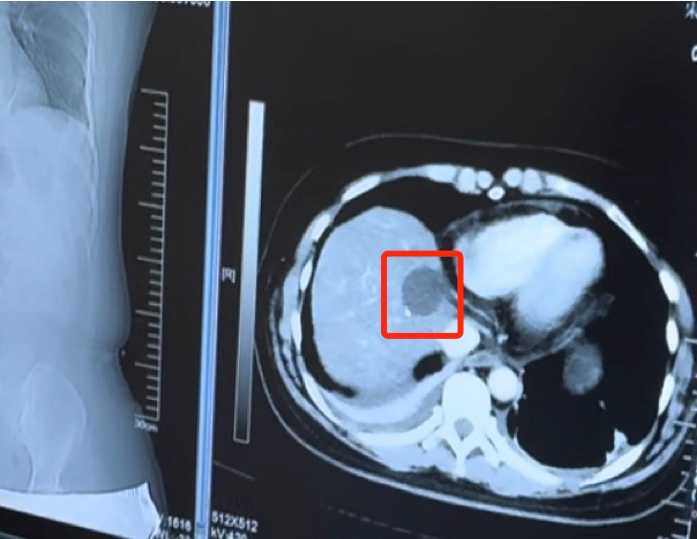

△肝癌消融术后肿瘤被清理干净肺癌,实施射频消融

80岁的李先生(化名)有着长达40年的吸烟史。近几个月来,他时常感到胸闷、气短,并伴有持续性的咳嗽和少量血痰,经检查后确诊患有肺癌,肿瘤位于右肺上叶,直径约2.5厘米。考虑到患者年龄和身体状况,庄兴俊主任团队制定了化疗、靶向治疗、射频消融等综合治疗方案。术中,通过高能微波直接作用于肿瘤组织,产生高温使其坏死。术后随访CT显示患者肿瘤完全坏死,身体状况稳定。